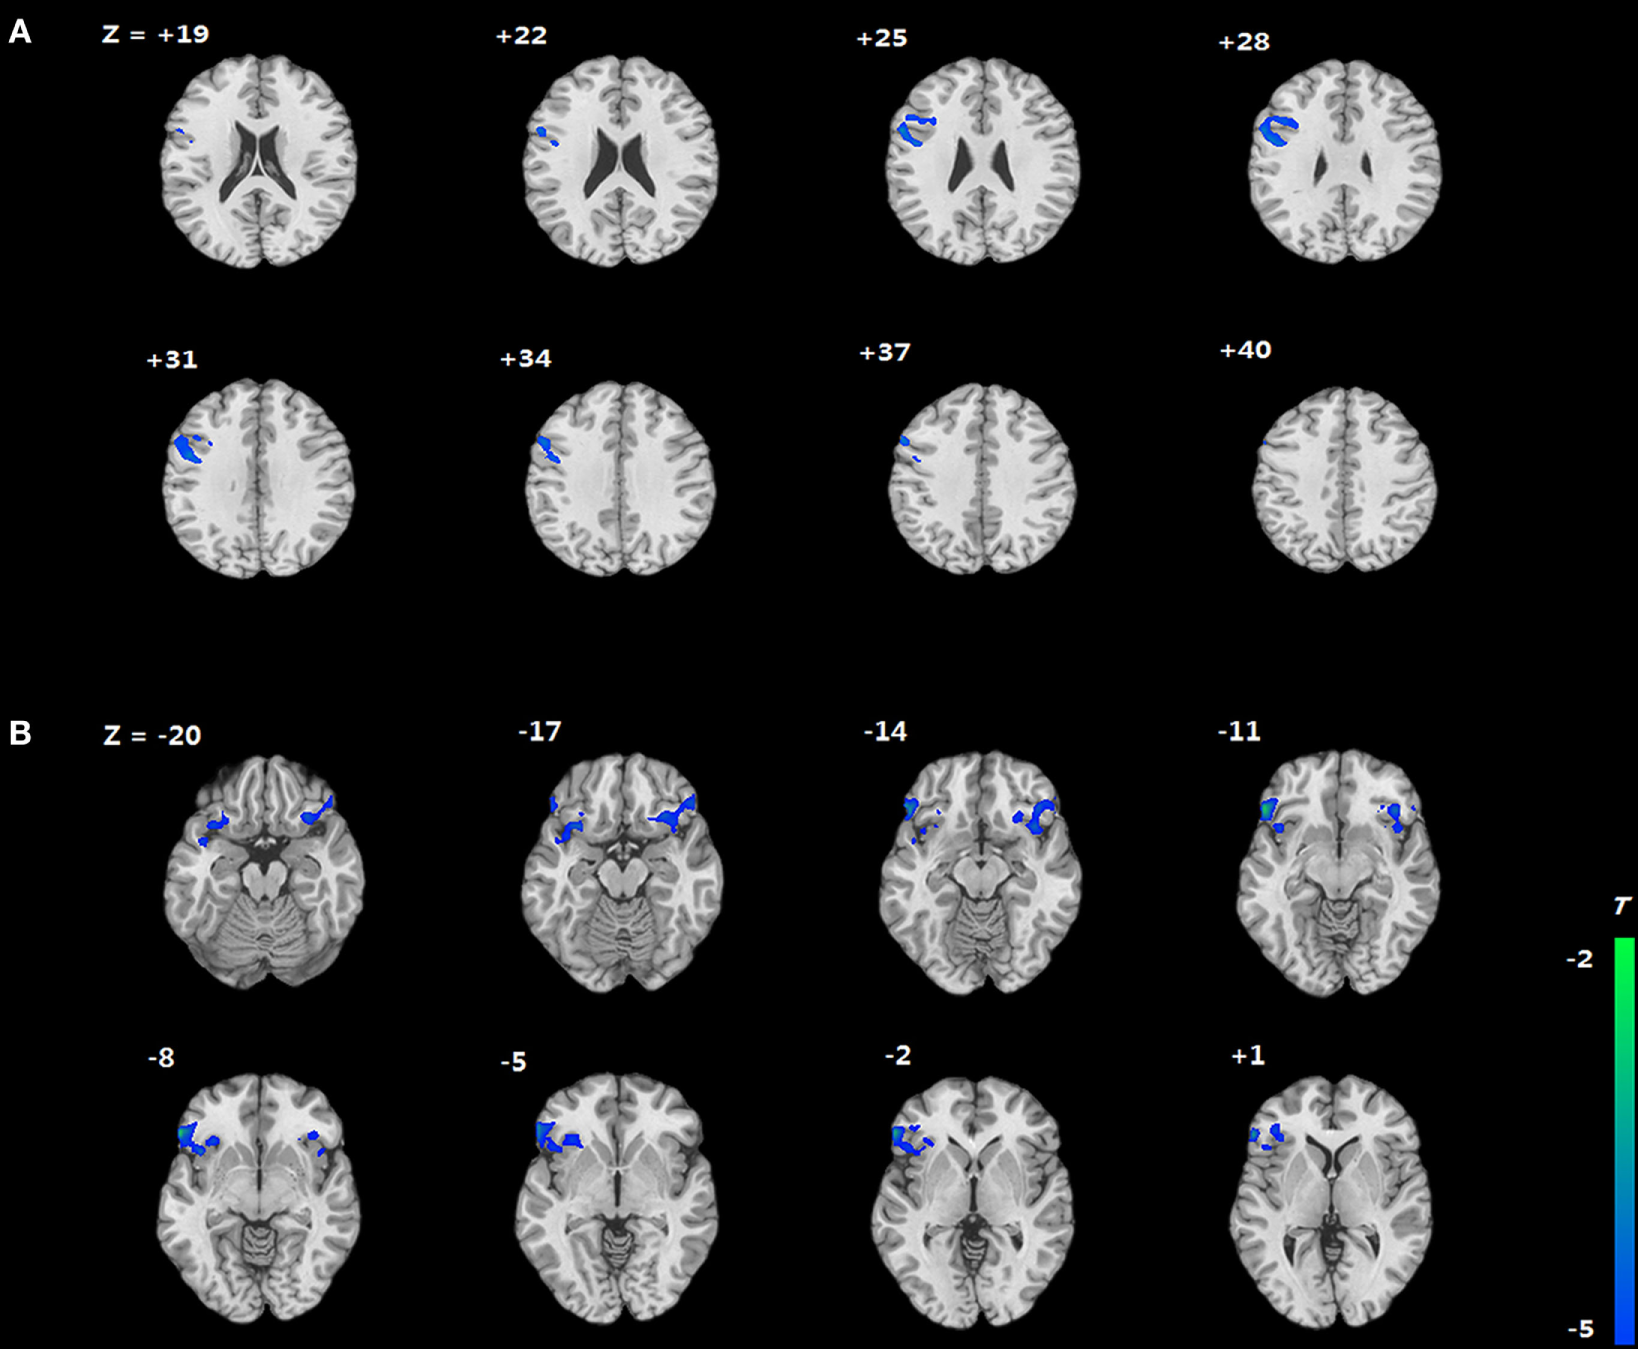

We compared the two groups in terms of BOLD signal differences between delayed choices and immediate choices. Group comparison suggested that the IGD showed smaller BOLD signal differences, between delayed and immediate choice, over the left DLPFC and bilateral IFG than HC (Figure 4 and Table 2), which was consistent with our hypothesis. Nevertheless, the IGD did not show any greater BOLD signals in the whole brain compared to HC. In each group, the IGD showed greater brain activations in the anterior cingulate gyrus and lower brain activations in the left IFG and medial frontal gyrus for delayed choices than immediate choices; the HC showed greater brain activations in the right IFG, orbital gyrus, and middle frontal gyrus for delayed choices than immediate choices (Figure 5 and Table 3).

Figure 4. Brain areas showing differences in Internet gaming disorder (IGD) when comparing to healthy control (HC) [(IGDdelay − IGDimmediate) − (HCdelay − HCimmediate)]. (A) IGD show lower brain activation in left dorsolateral prefrontal cortex than HC. (B) IGD show lower brain activation in bilateral IFG than HC.